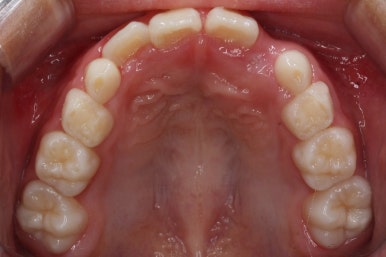

우선 처음 내원 하셨을 때의 입안의 상태를 보겠습니다.

아직 나이가 어리다 보니 곳곳에 유치가 남아 있었어요. 보통 이렇게 영구치가 다 나오지 않았을 경우, 보호자분들은 "치아교정"에 대해서는 전혀 생각해 보시지 않으셨을 수 있어요.

이번 환자분의 경우도 앞니가 거꾸로 물리는 상황이어서 치료가 필요한 상황이였습니다.